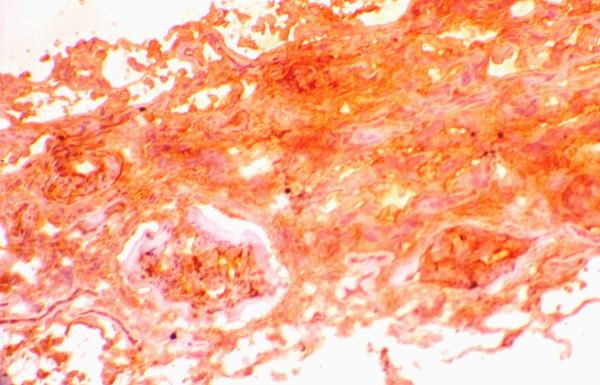

Small vessel vasculitides are known to follow a devastating course towards end-stage renal disease, unless treated with immunosuppressive regiments. We investigated the value of clinical, histological and immunohistochemical parameters as predictors of outcome at diagnosis in patients with pauci immune necrotizing glomerulonephritis.

In 34 patients the percentage and evolution stage of crescents, the presence of glomerular necrosis, the degree or severity of arteriosclerosis, as well as the extent of tubulointerstitial infiltration, interstial fibrosis and tubular atrophy were assessed. Monoclonal antibodies were used to identify infiltrating macrophages, alpha-SMA(+) and PCNA(+) cells, the expression of integrins alpha3beta1 and LFA-1beta, the adhesion molecule ICAM-1, the growth factor TGF-beta1 and the terminal complement component C5b-9.

24 pts (70.6%) showed a complete or partial response to the treatment. The follow-up period was 20 +/- 22 months. At multivariate analysis, serum CRP (p = 0.024), the intensity of tubular expression of C5b-9 (p < 0.0001) as well as the extent of glomerular and tubular expression of alpha3beta1 integrin (p = 0.001 and 0.008 respectively) independently predicted the response to treatment. The response rate was better in ANCA(+) pts (p = 0.008). The extent of interstitial infiltrate (p < 0.0001), the severity of tubulointerstitial fibrosis (p < 0.0001) and the severity of tubular TGF-beta1 expression (p < 0.0001) were independent predictors of long term outcome of renal function.

Patients with ANCA-associated renal vasculitis seem to respond better to the treatment. Acute phase reactants, such as CRP, implying a more intense parenchymal inflammatory reaction, as well as the intensity of the de novo expression of C5b-9 and the glomerular and tubular expression of alpha3beta1 integrin predict the response to therapy. The severity of TIN lesions and of the tubulo-interstitial TGF-beta1 and C5b-9 expression predict an unfavourable outcome.